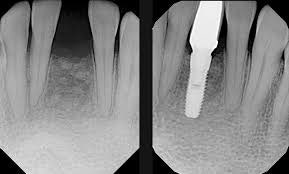

🩵 2단계 — 임플란트 픽스처(뿌리) 식립: 실제 ‘수술’은 여기예요

임플란트 수술 과정의 핵심은 바로 이 식립 단계입니다.

뼈 상태를 3D CT로 확인한 후

가장 안전한 각도와 깊이로 티타늄 픽스처(Fixture)를 심게 돼요.